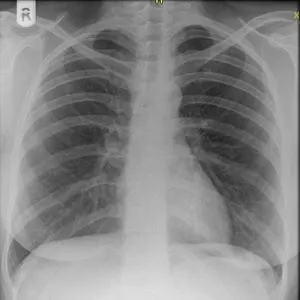

In the intensive care setting, a restrictive approach to ordering chest x-rays can provide positive outcomes, according to a study from Mount Sinai Beth Israel, in New York, NY. Results found that a restrictive approach led to large decreases in total chest x-rays (CXRs) ordered, correcting for both total number of patients and ventilator days.

A restrictive approach to ordering chest x-rays in the intensive care unit (ICU) appears to be a safe practice that leads to a significant reduction in radiation exposure and ICU operating costs, according to researchers. The study is published in the CHEST Journal, an official publication of the American College of Chest Physicians.

Chest radiographs are routinely performed in the ICU for mechanically ventilated patients; however, the utility of this practice remains unclear and is surely not evidence based. Faced with rising costs of modern medicine, intensivists must balance delivering both excellent and cost conscious care.

A quality improvement inititative recommending a restrictive approach to ordering CXRs was implemented at a teaching hospital in January 2012. It consisted of monthly education for ICU providers on more focused indications for CXR use including ICU admission, post procedure, or change in clinical status. A retrospective review was later conducted of all ICU patients from 2011-2014 to examine the effectiveness of the initiative.

According to the results, implementation of a restrictive approach to ordering CXRs led to large decreases in the total number of CXRs ordered while corrected for both total numbers of patients and ventilator days. The researchers observed a 164 percent reduction in total number of CXRs ordered between 2011 and 2014. In addition, there was no negative impact on total number of patient ventilator days, length of ICU stay, and other outcomes.

"A restrictive approach to ordering chest x-rays in the ICU appears to be a safe practice," says lead researcher Jason Filopei, MD, Mount Sinai Beth Israel. "We believe it will lead to a significant saving of hospital resources."